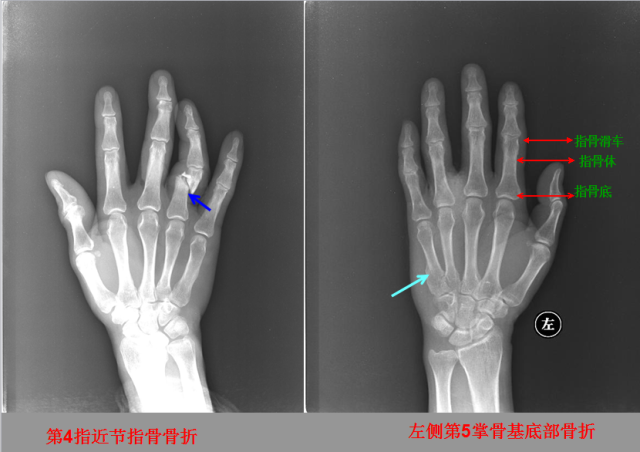

骨折篇

01

定义:骨折{Fracture}是指骨的完整性和连续性的折裂或粉碎。包括创伤性骨折、疲劳性骨折和病例理性骨折。 临床上以创伤性骨折*常见。